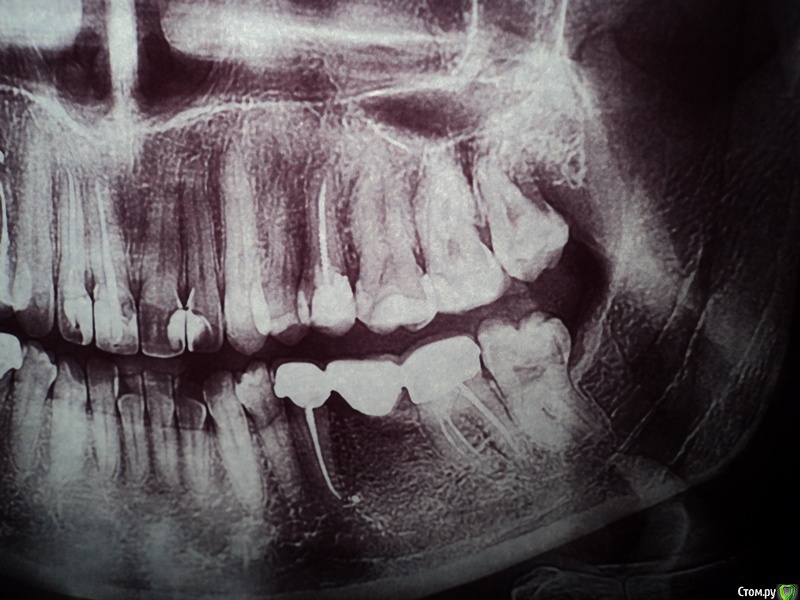

Анэйтис Опубликовано 5 февраля, 2015 Поделиться Опубликовано 5 февраля, 2015 (изменено) Добрый день!Четыре года назад мне были удалены 36 и 46 зубы (шестые нижние). Поставили мосты. Недавно начал ныть 37 зуб (нижний левый).Мост слетел. В 37 зубе - вторичный кариес. К тому же этот зуб, как выяснилось - наполовину пломба, наполовину сам дентин. Я опасаюсь, что если начать его лечение, остатки дентина могут отколоться до десны. И мост поставить будет, грубо говоря, не на что. Какие варианты лечения есть в таком случае? Можно ли сделать вкладку и на нее установить мост снова? Будет ли надежной такая конструкция, учитывая то, что зуб - жевательный. Очень хотелось бы услышать ваше мнение по поводу ситуации с 35, 37 и 45, 47 зубами.И еще очень интересуют 18, 28, 38, 48 зубы - удалять или еще что-то можно спасти? Изменено 5 февраля, 2015 пользователем Анэйтис Ссылка на комментарий

SDC Опубликовано 5 февраля, 2015 Поделиться Опубликовано 5 февраля, 2015 Добрый день!Четыре года назад мне были удалены 36 и 46 зубы (шестые нижние). Поставили мосты. Недавно начал ныть 37 зуб (нижний левый).Мост слетел. В 37 зубе - вторичный кариес. К тому же этот зуб, как выяснилось - наполовину пломба, наполовину сам дентин. Я опасаюсь, что если начать его лечение, остатки дентина могут отколоться до десны. И мост поставить будет, грубо говоря, не на что. Какие варианты лечения есть в таком случае? Можно ли сделать вкладку и на нее установить мост снова? Будет ли надежной такая конструкция, учитывая то, что зуб - жевательный. Очень хотелось бы услышать ваше мнение по поводу ситуации с 35, 37 и 45, 47 зубами.И еще очень интересуют 18, 28, 38, 48 зубы - удалять или еще что-то можно спасти? Здравствуйте.Снимок, который Вы предоставили слишком контрастный, по этому снимку можно запросто ошибиться с первичной диагностикой кариеса зубов, но похоже, что 8-е зубы сохранять просто незачем.Тем не менее, правильным вариантом будет:имплантация в области отсутствующих нижних 6-х зубов и одиночные коронки на 5-е и 7-е зубы.Стоит подумать о протезировании коронками 15, 14, 25 зубов. Ссылка на комментарий

Анэйтис Опубликовано 5 февраля, 2015 Автор Поделиться Опубликовано 5 февраля, 2015 Вариант с имплантами пока не рассматриваю, так как я курю. А это - противопоказание в этом случае, как я знаю. Какие варианты реставрации, помимо имплантов, возможны?И почему 8-е зубы сохранять незачем? Они - не в прикусе или слишком разрушены? Ссылка на комментарий

Saymon Опубликовано 20 февраля, 2015 Поделиться Опубликовано 20 февраля, 2015 (изменено) У меня в 37 - очень большая пломба. Практически на 2/3 зуба. Сам этот зуб (37) - опорный под мостиком (37 - 35). Между пломбой и самой тканью зуба по стенке - кариес. Можно ли поставить в него культю и на нее снова "посадить" мост назад? Будет ли такая конструкция надежной?1. Нужно определиться с самими зубами. Перелечивать или нет. Для этого нужны прицельные снимки.2. Определиться с методом восстановления культи зуба, после перелечивания(культевая вкладка, либо просто пломба).3. Выбрать вариант восстановления зубов:а) изготовить в любом случае новые мостовидные протезы. Старые можно выкинуть. ИЛИб) изготовить отдельно стоящие коронки на зубы, которые были под мостами и установить имплант с коронкой в область отсутствующего зуба.4. Восьмерки удалять.P.S. Подзамазать, подшаманить и посадить мост обратно технически можно, но не надолго. И через некоторое время варианты лечения будут другие, а это бОльшое количество имплантов или съемные протезы и никаких мостов. Изменено 20 февраля, 2015 пользователем Saymon Ссылка на комментарий